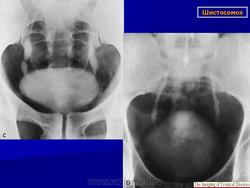

Бильгарциоз (Schistosomiasis) мочевого пузыря